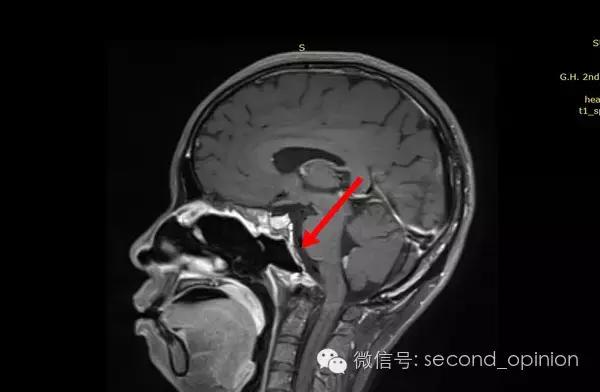

2015年1月25日 对比质子治疗之前增强核磁共振影像无明显变化,脊索瘤放疗后变化缓慢,建议3月后继续复查。

2015年04月01日 对比增强核磁共振影像,同第一次复查。

2015年06月03日 对比增强核磁共振影像,对比第三次复查,肿瘤略有缩小。

质子治疗后第四次复查

目前患者生活质量良好,无复发转移。